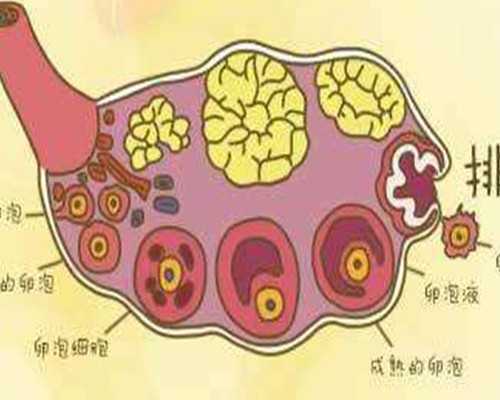

只要女性到了40歲以上,試管嬰兒成功與否的決定因素就取決于 "卵巢功能"。隨著年齡的增長,女性的卵巢功能會逐漸衰退,卵子的質量也會隨之下降。高齡婦女在懷孕前需要對自己的生育能力進行評估,以便做好充分的心理準備,為優生優育做好準備。